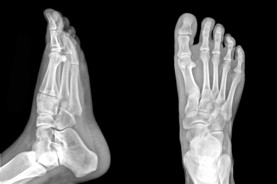

Foot Doctor Calgary & Foot Pain Specialists

The Foot Institute is an association of Calgary Doctors specializing in the medical treatment of the foot and ankle, and is one of the largest groups of foot specialists in Alberta.

The Calgary Foot Institute is dedicated to the medical and surgical treatment of the foot. Our mandate is to provide the best possible medical, surgical and preventative treatment available for our patients. We do this by providing well-trained Doctors who are committed to treat and prevent all types of foot pain, biomechanical disorders, as well as all other problems relating to the feet.

At the Calgary Foot Institute, our Doctors are trained to specifically treat problems associated with your feet or ankles. Below are several of the most common problems that we see on a day to day basis: